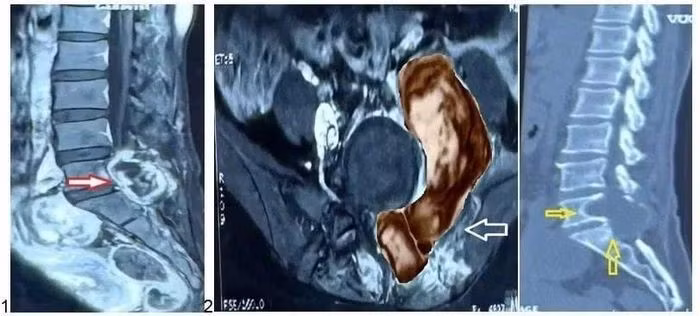

Kết quả chụp MRI tại Bệnh viện Nhân dân 115 cho thấy khối u lớn vùng L5-S1, xâm lấn cơ cạnh sống, cánh chậu và phúc mạc, đúng vị trí phẫu thuật cũ - nghi ngờ ác tính.

Khối u ác tính vùng cột sống thắt lưng của bệnh nhân. Ảnh BV